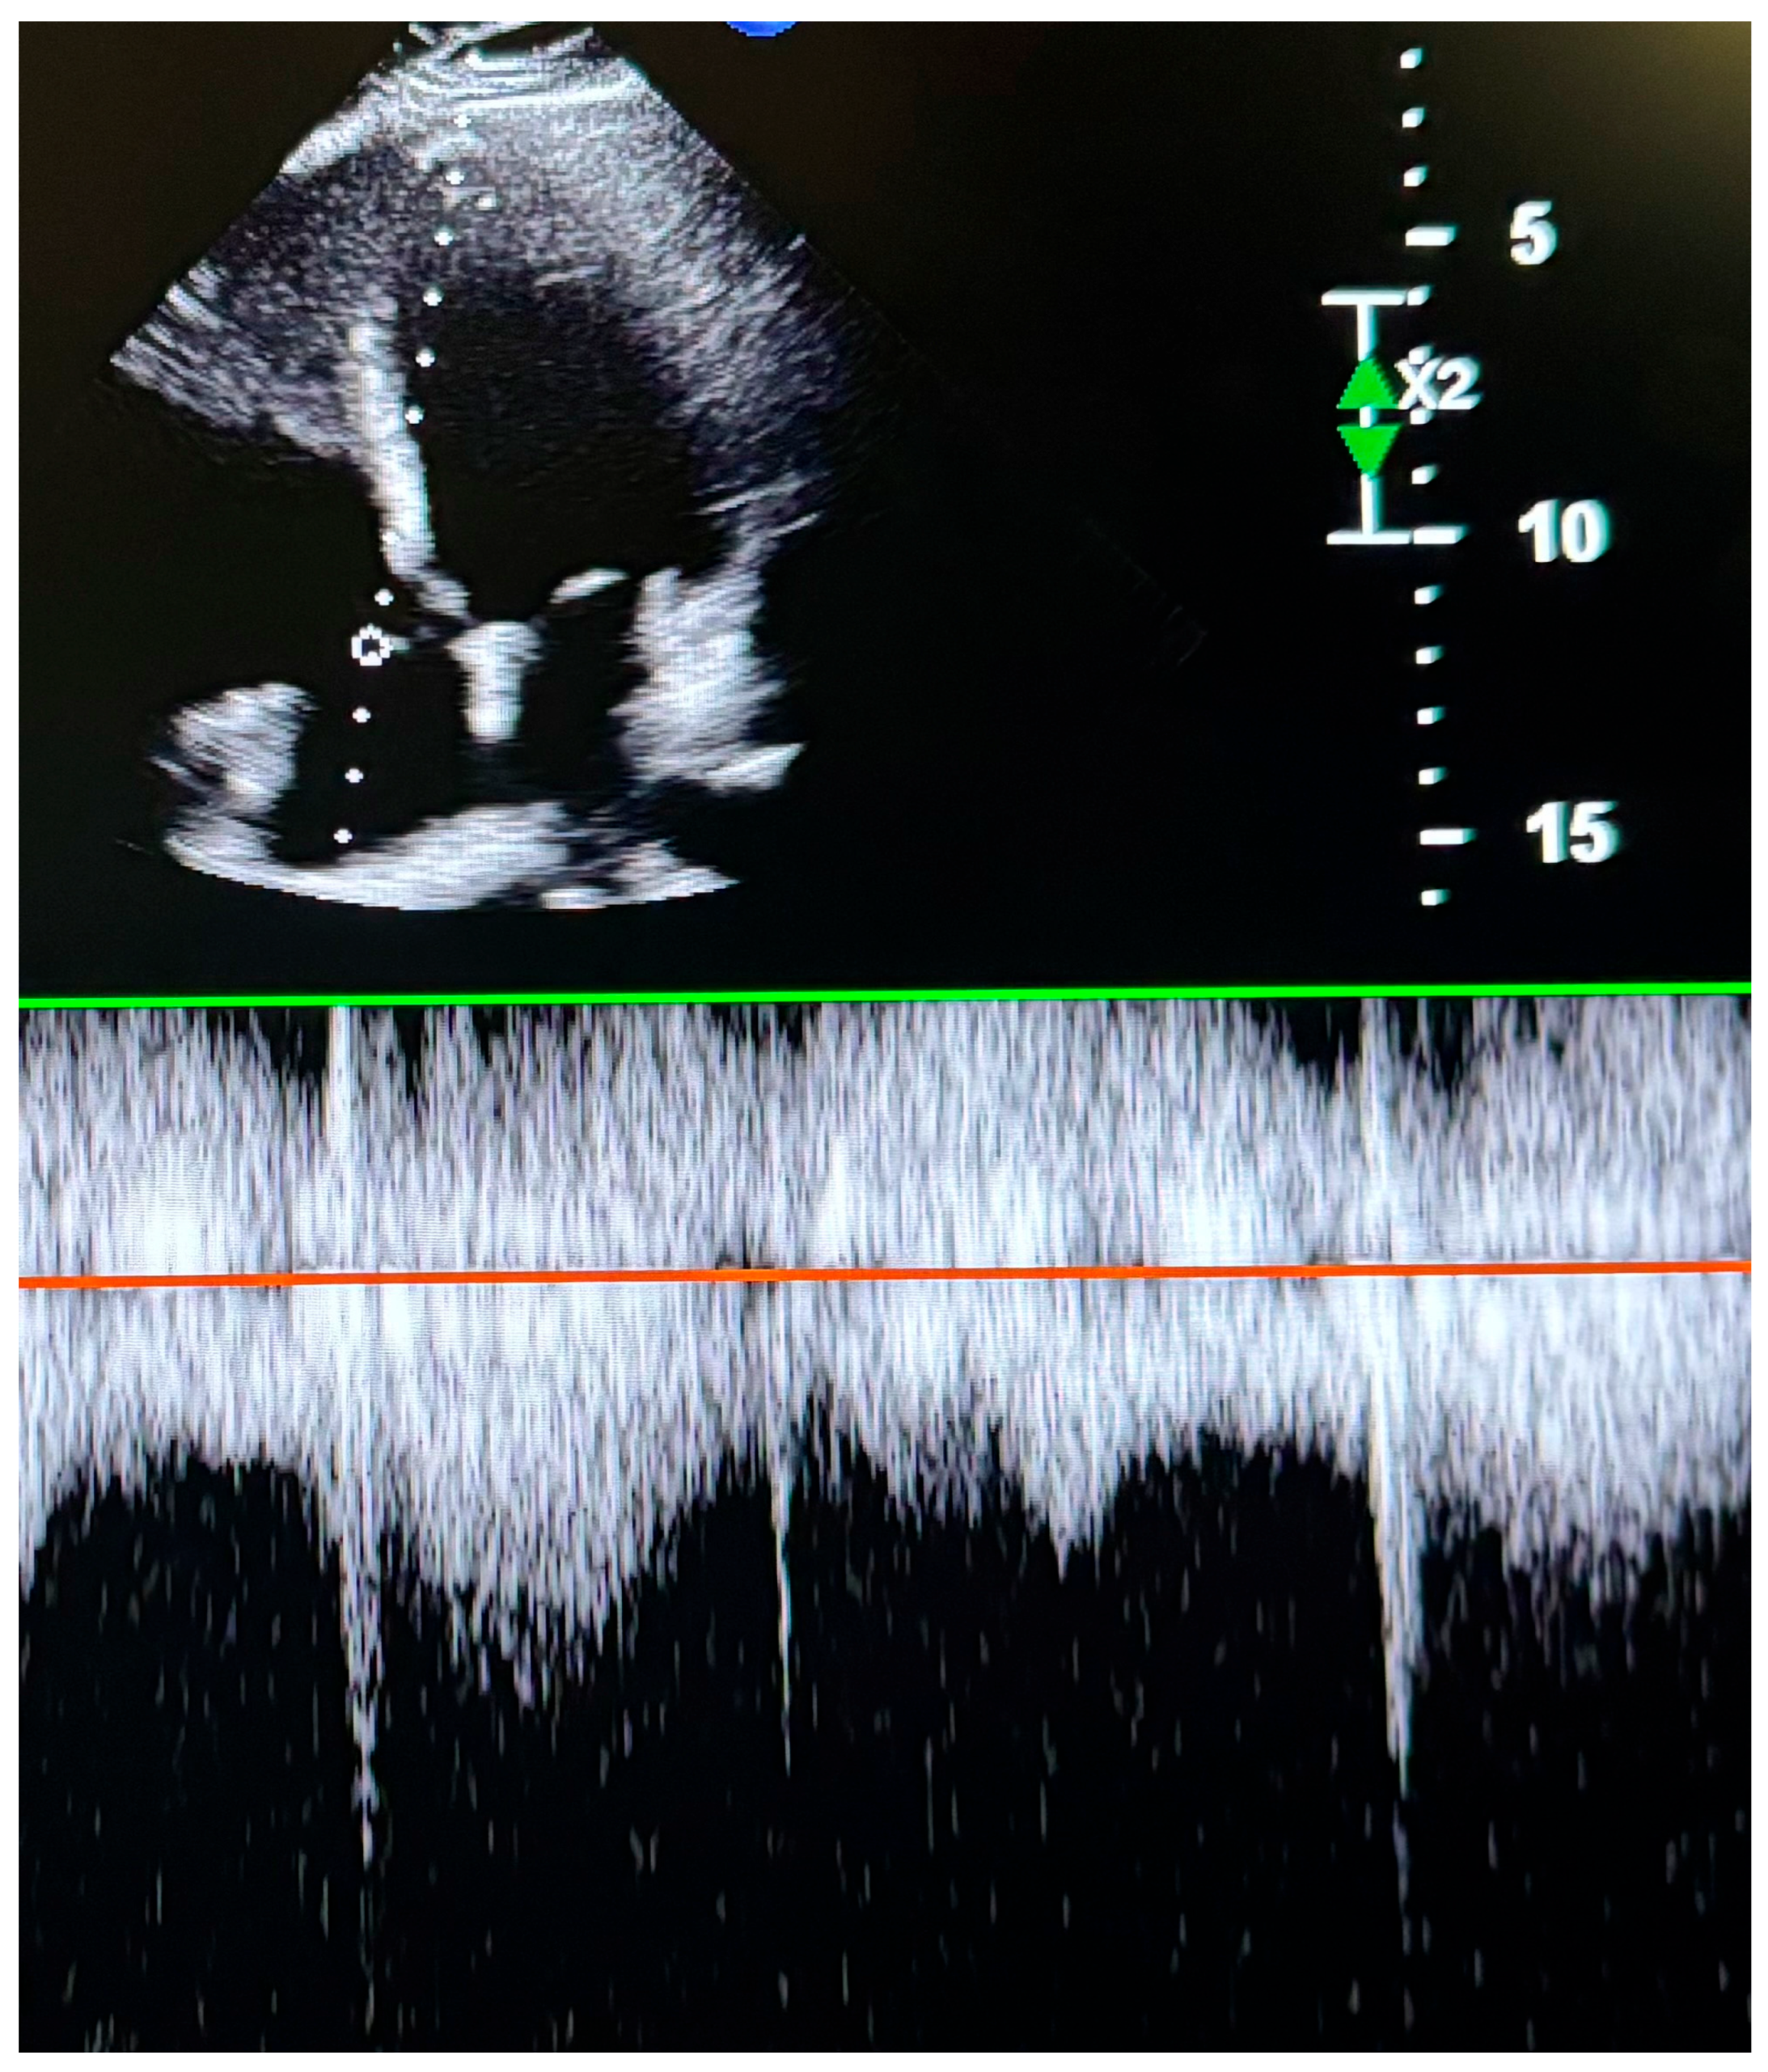

2.3. Transthoracic Echocardiography (TTE) and Data Collection

| PASP | 11.31 (9.25–14.35) | 13.76 (10.56–21.59) | 0.026 |

| TAPSE/PASP | 2.29 ± 0.81 | 1.63 ± 0.68 | <0.001 |